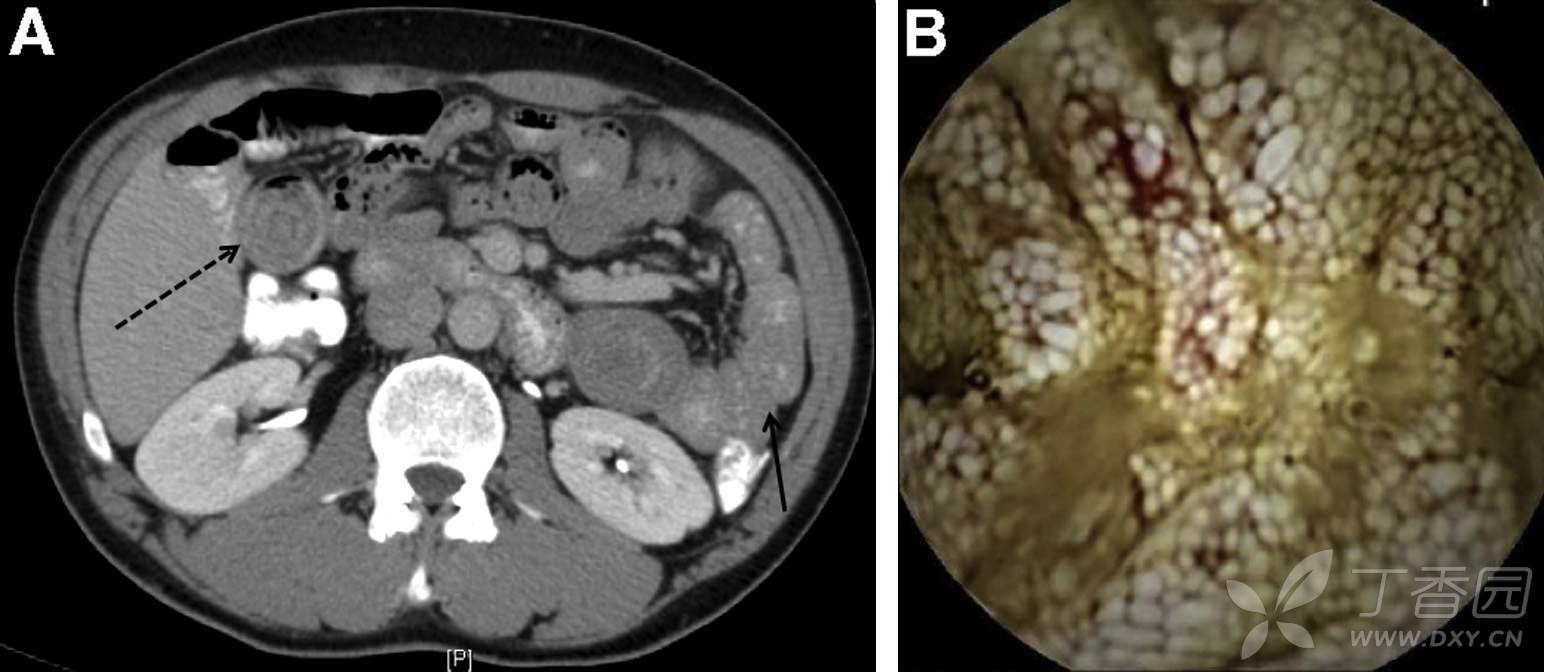

辅助检查:血常规正常,ALB 32/L, K+ 2.9 mEq/L。HIV阴性,血胆固醇、皮质醇水平正常。腹部增强CT及胶囊内镜所见如下图(图A,B)。结肠镜所见结肠及回肠末端正常。小肠镜检查证实胶囊内镜所见,并取多处活检。

1、描述CT及胶囊内镜所见;